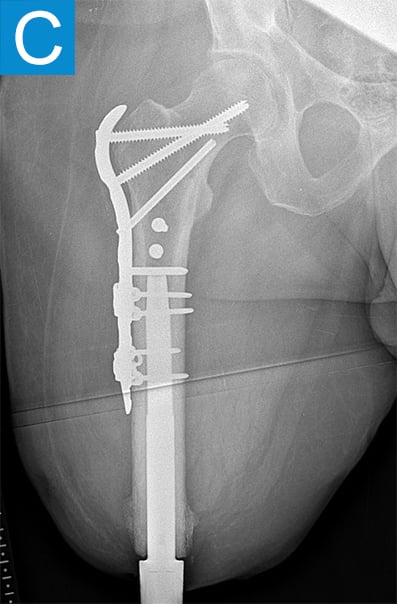

Standing radiographs showed periosteal reaction to the distal femoral isthmus, and given the chronicity of his infections the decision was made to stage the transfemoral amputation and osseointegration implant insertion (Figure 1b). During the amputation, the tibial and peroneal nerves underwent targeted muscle reinnervation to the motor branches of the medial and lateral hamstrings, respectively. Cement mixed with tobramycin and vancomycin was placed in the femoral canal, and the remaining musculature was purse stringed around the residual femur. His proximal cultures were negative, and so no further antibiotic treatment was given. Approximately 8 weeks later, the antibiotic spacer was removed and a press fit femoral osseointegration implant was placed in a percutaneous procedure (Figure 2a). Cultures of the canal remained negative.

Figure 1. Preoperative X-rays show (A) static cement spacer on antibiotic suppression and (B) an antibiotic cement spacer in the residual femur.

He started progressively loading the implant at 2 weeks and received his full prosthetic leg with simple hinged knee at 6 weeks. At 3 months he no longer used assist devices and at 3.5 months his prosthesis was changed to a microprocessor-controlled knee. Shortly after receiving the new knee, he stumbled stepping over a ledge and fell, sustaining a subtrochanteric proximal femur fracture (Figure 2b). The fracture extended to the tip of the implant, which remained stable in the bone. He underwent open reduction and internal fixation of the femur fracture with a proximal locking plate (Figure 2c). He did not wear the prosthetic leg for 10 weeks, when he began gradually loading the femur. He resumed full weightbearing without assistive devices about 6 weeks later.

Figure 2. Postoperative X-rays shows (A) a femoral osseointegration implant; (B) a subtrochanteric proximal fracture; (C) the femur fracture repaired by open reduction and internal fixation with a proximal locking plate.